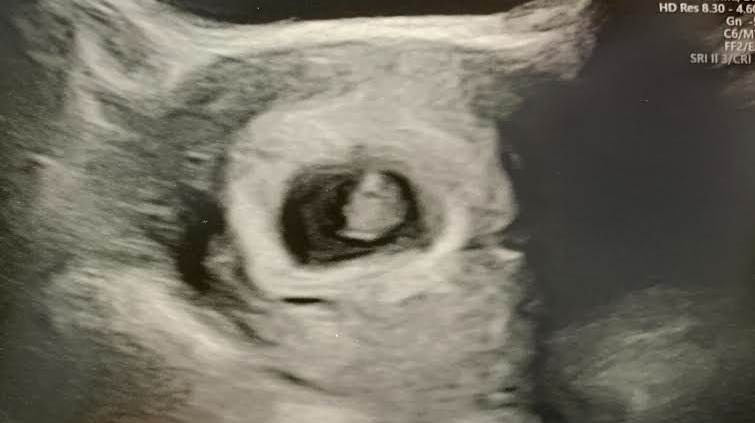

I was not expecting the gel to be warm! I jumped a little because of it. For some reason I was expecting it to be cold. Now before we went to the appointment, I had read that I needed to fill my bladder up because I was going to have to pee in a cup. Not true. So as she started pressing down with the thingy that looks inside your uterus, she pointed out my very full bladder that she could see on the machine and apologized. After a second of rooting around, there they were! They were a tiny grey spot, and you could see a tiny moving speck that was their heartbeat!

That is what I was so afraid of, not seeing a heartbeat. And poof, out those fears went with this tiny fluttering speck on a big screen. She told us our initial estimate was wrong, that we were actually 7 weeks, 2 days pregnant. So if you read my earlier posts, just know the weeks are a little off. She was able to tell us this by looking at a grey blob and measuring them. They came in at 1.13 cm, and their heartrate was 148 bpm, which is apparently perfect. So now we know, we so far have a healthy human, and one human, which is what we want! And we got pictures with a promise that next time at around 12 weeks, we would be able to see a lot more.